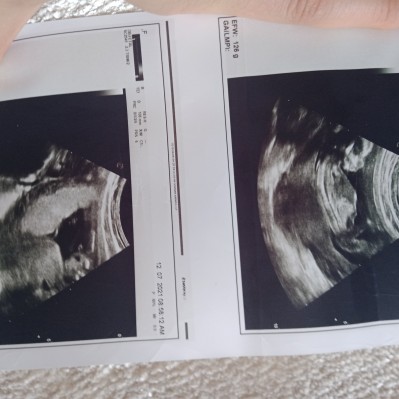

Kızlar doktorum %90 erkek dedi eve geldim ultrasyon kağidina bakıyorum sanki pipisi ve hay.. lari sanki sizce

Gebelik haftası 16+1

Ya bacak arasın aşağı doğru olan kısımda sanki taş.. lari var gibi gelmişti di de

Ultrasyonda çıkıntı vardı işte eve geldim sanki böyle attığım resimde taş.. lari var gibi

Keşke 2 ayrı doktor da erkek dedi ama burda utrasyonda gördüğüm çıkıntı yok

%90 erkek dedi canım bende çıkıntiyi gördüm aslinda ama burda bı değişik